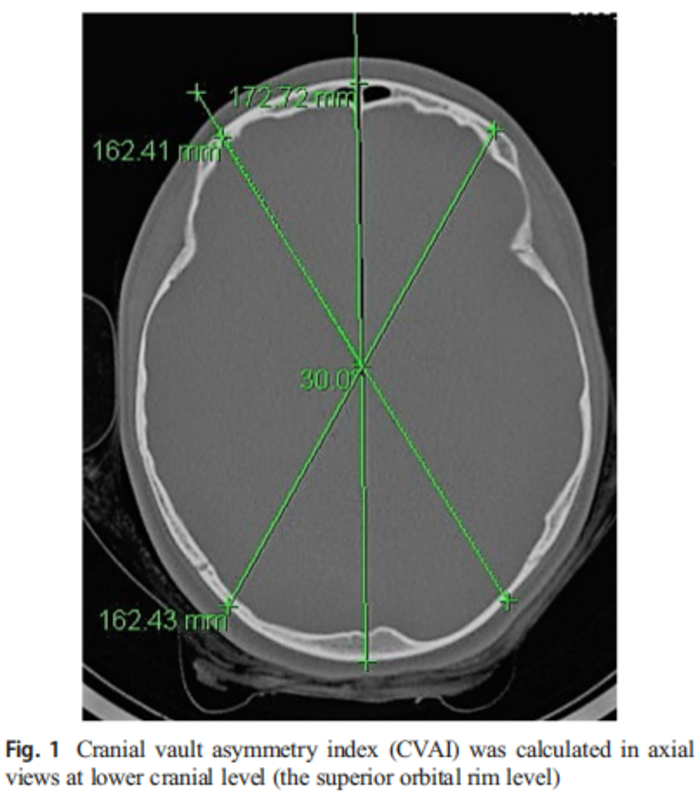

婴幼儿及青少年姿势性斜头畸形的患病率和严重程度 - 微医(挂号网)

图片尺寸700x804